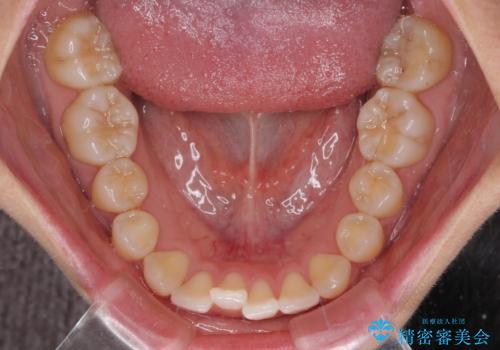

- 上顎前歯の隙間を気にして来院された患者様です。

下顎前歯が上顎前歯に食い込むような咬み合わせにより、上顎前歯が開いてしまっていたため、咬合高径の挙上により突き上げを改善するよう、インビザラインにより矯正治療を行うこととしました。

咬合高径の挙上により上顎前歯の突出感も改善することができ、整った口元となりました。